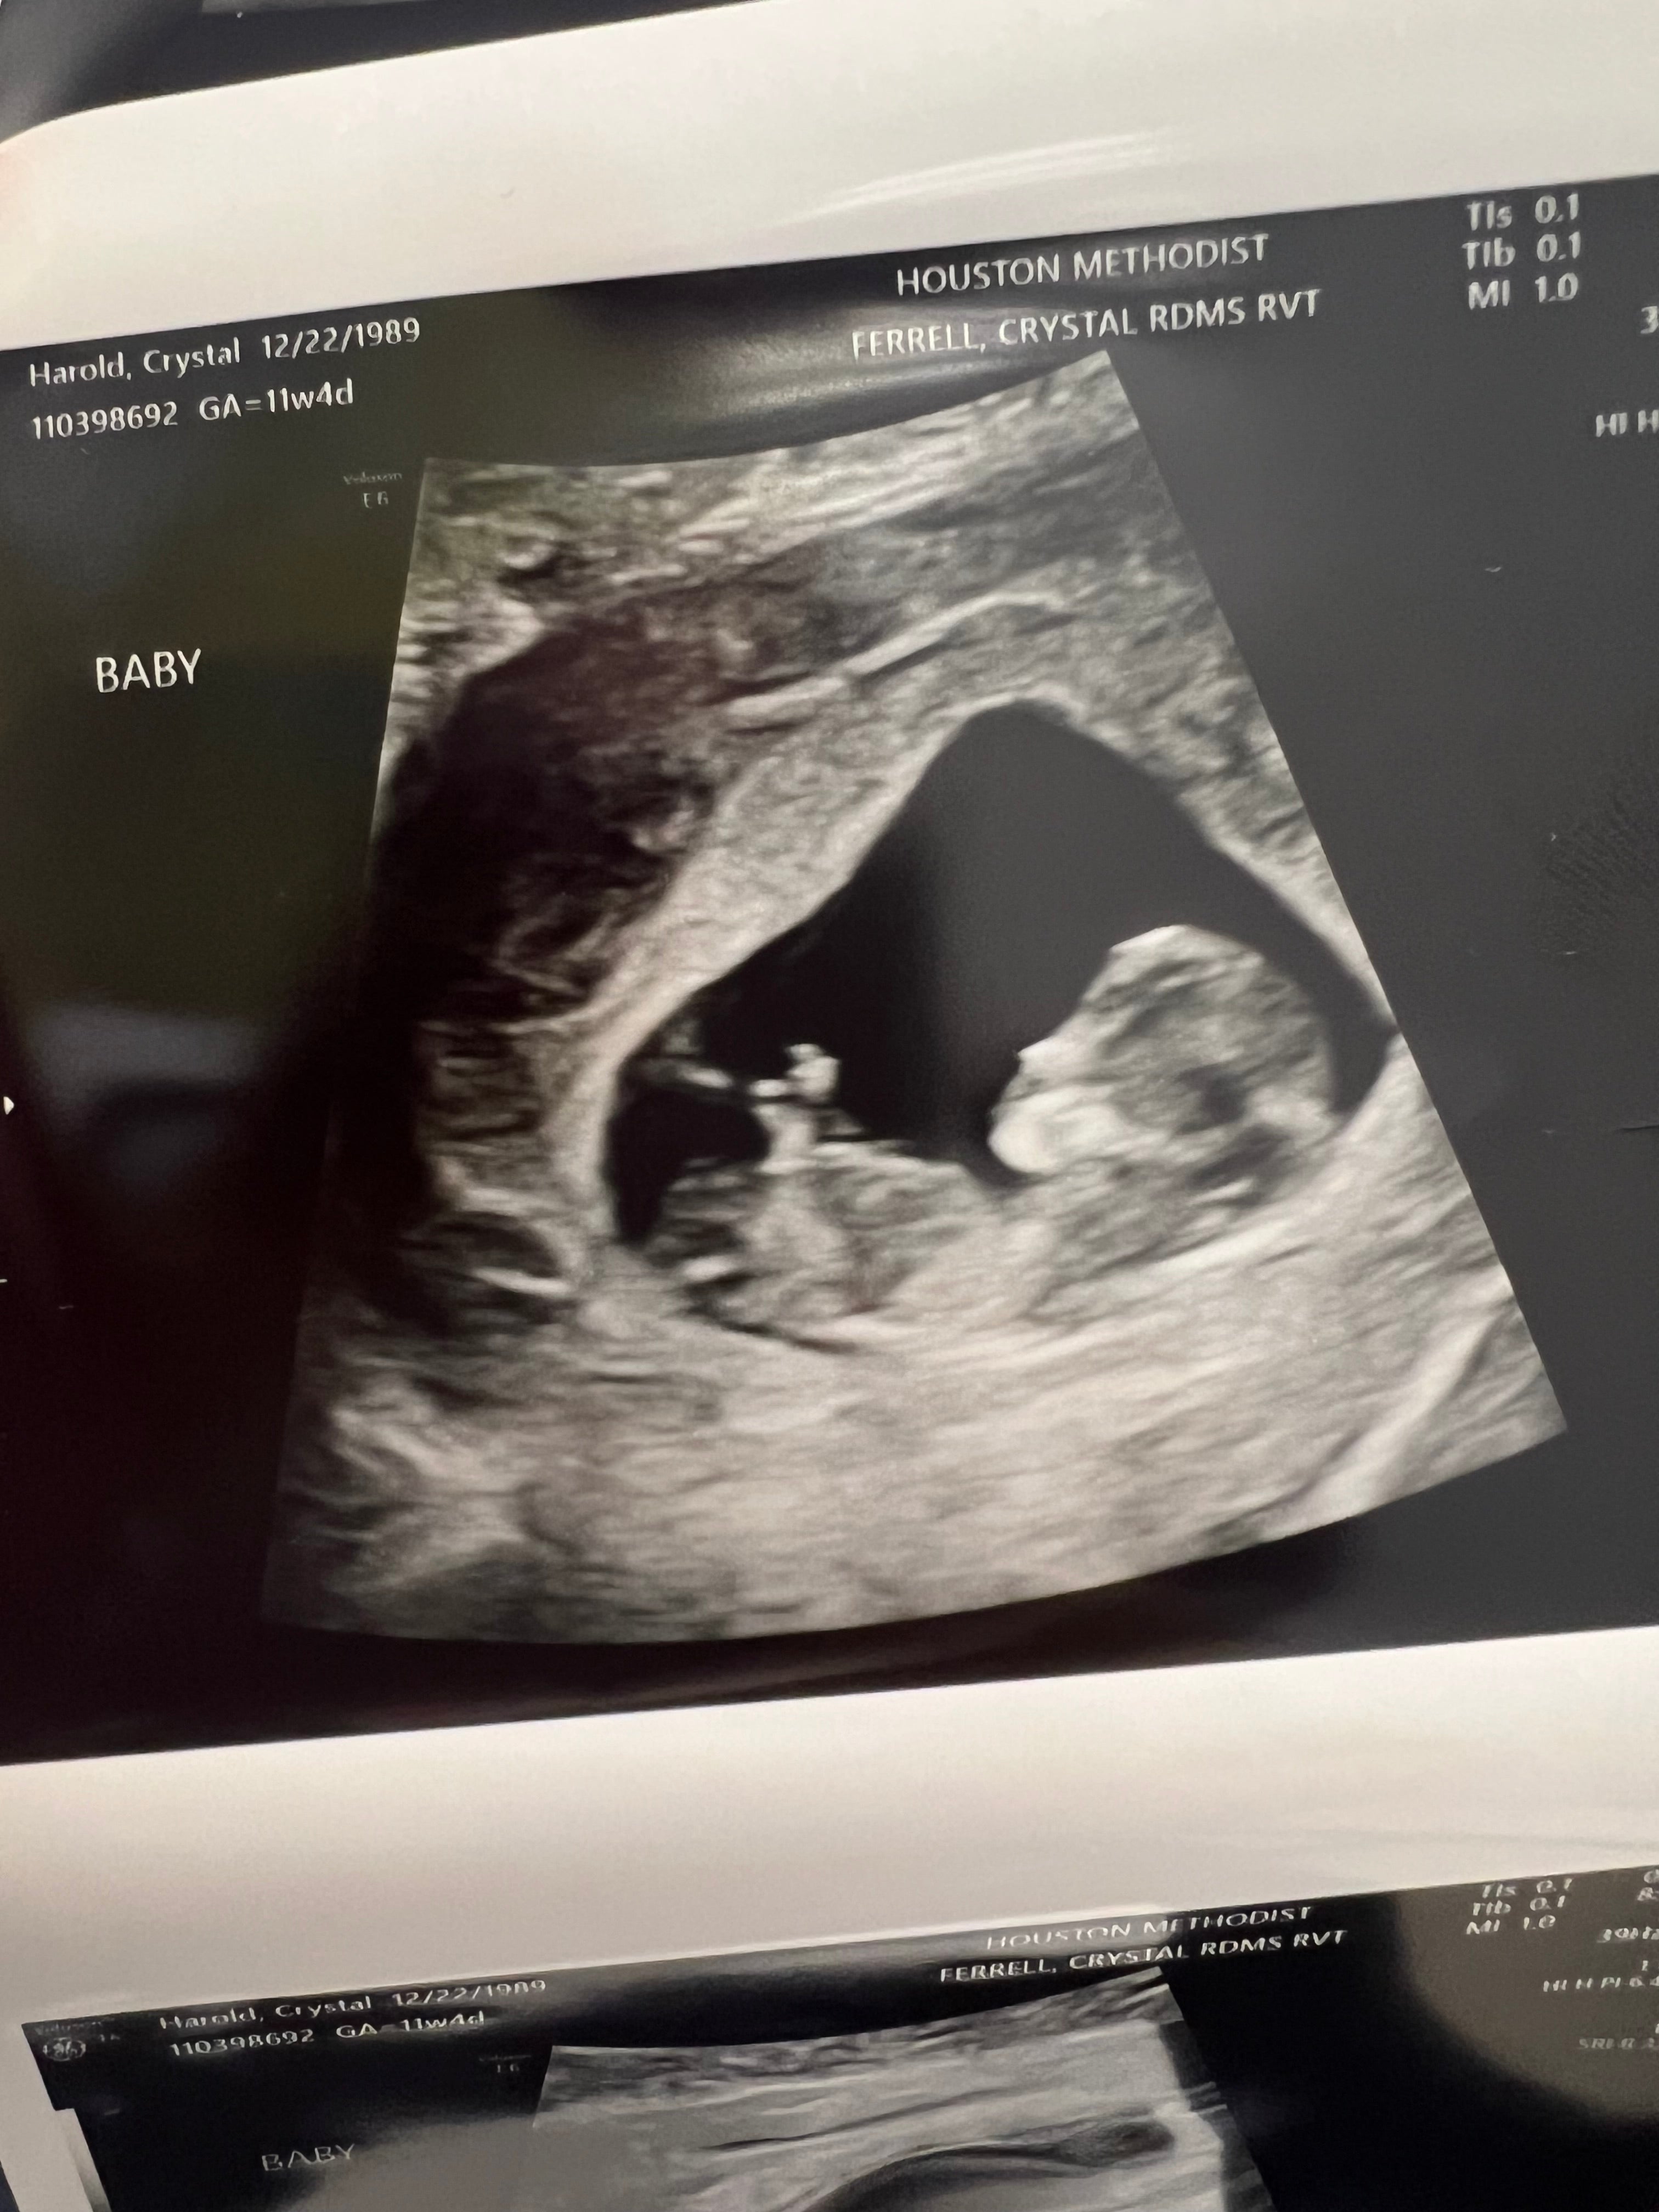

Last year (January 2022), we purchased Mosie Baby and on the second try, I conceived. I was 10 weeks along and then miscarried. That was, of course, devastating- but we knew we wanted to try again. We waited another year and then this year (January 2023) we tried again and conceived after our first try- using the ovulation tests, as well as the applicator kit. It was simple to use and clear directions. I’m now 13 weeks along after confirming in two different ultrasounds that there is a heartbeat and a growing baby. We are so grateful to Mosie Baby for making our goal of starting a family more simple.